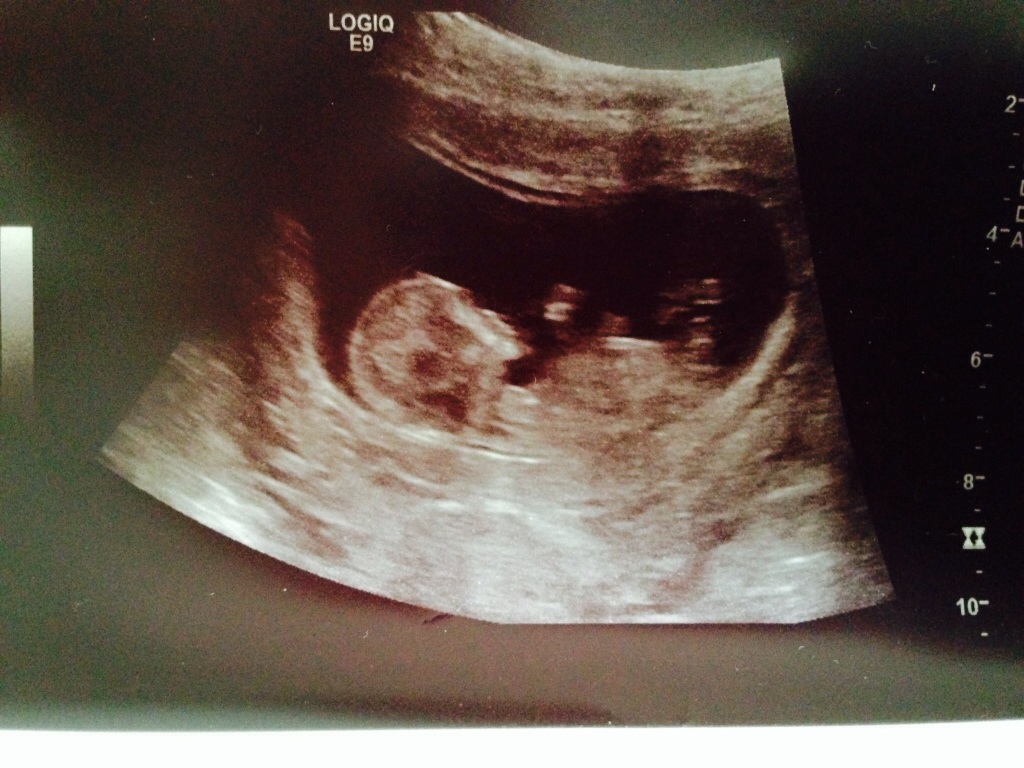

That's a girl!!!

Yes I guess girl too

Pink Bundle!

Pink